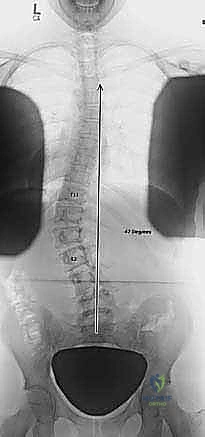

2. التصوير بالأشعة السينية (X-Rays)

هو المعيار الذهبي لتشخيص الجنف. يتم التقاط صور شعاعية لكامل العمود الفقري (من الرقبة إلى الحوض) من الأمام والخلف والجانب، والمريض في وضع الوقوف. من خلال هذه الصور، يقوم الدكتور هطيف بـ:

* قياس زاوية كوب (Cobb Angle): وهي الزاوية التي تحدد شدة الانحناء. الانحناءات الأكبر من 10 درجات تُعتبر جنفاً.

* تقييم النضج العظمي (Risser Sign): من خلال فحص عظام الحوض لمعرفة ما إذا كان المريض لا يزال ينمو، مما يساعد في التنبؤ باحتمالية تدهور الانحناء.